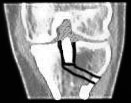

Immerhin scheinen meine Knochen eine Art Schnellheilungsmechanismus zu haben: Nur 5 Wochen nach der Korrekturoperation ist der Knochen schon fast wieder ganz verheilt - im folgenden Bild aus dem Inneren des Knies ist links das Bild vom 3. Mai, rechts jenes vom 7. Juni. Das versetzte Stück der Eminenz ist fast wieder fest drin; die Lücke beim Pfeil hat sich deutlich verkleinert - Krücken ade, Schmerzen leider noch nicht ganz. Das Streckdefizit beträgt immer noch 12 Grad.